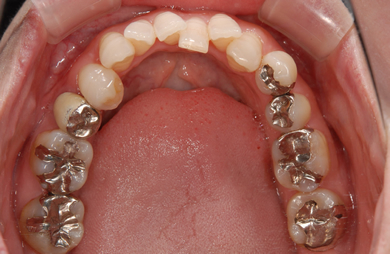

| 性別/年齢 | 女性 / 31歳 | ||||||||||||||||||||||||||||||||

| 主訴 | 歯並びを綺麗にしたい。 | ||||||||||||||||||||||||||||||||

| 治療方針 | 口元がきれいなので、なるべく横顔を変えないように歯を抜かずに治療を行う。しかし、下顎がだいぶ前に出ていて、上下の顎の前後的な位置のずれが大きいため、下顎にはインプラントアンカーを用いて、下の歯を本来の位置まで後ろに引っ張って治す。 | ||||||||||||||||||||||||||||||||

| 治療内容 | 唇側矯正(シルバー)、保定装置、矯正用スピードインプラント2本 | ||||||||||||||||||||||||||||||||

| 治療期間 | 1年5ヶ月 |